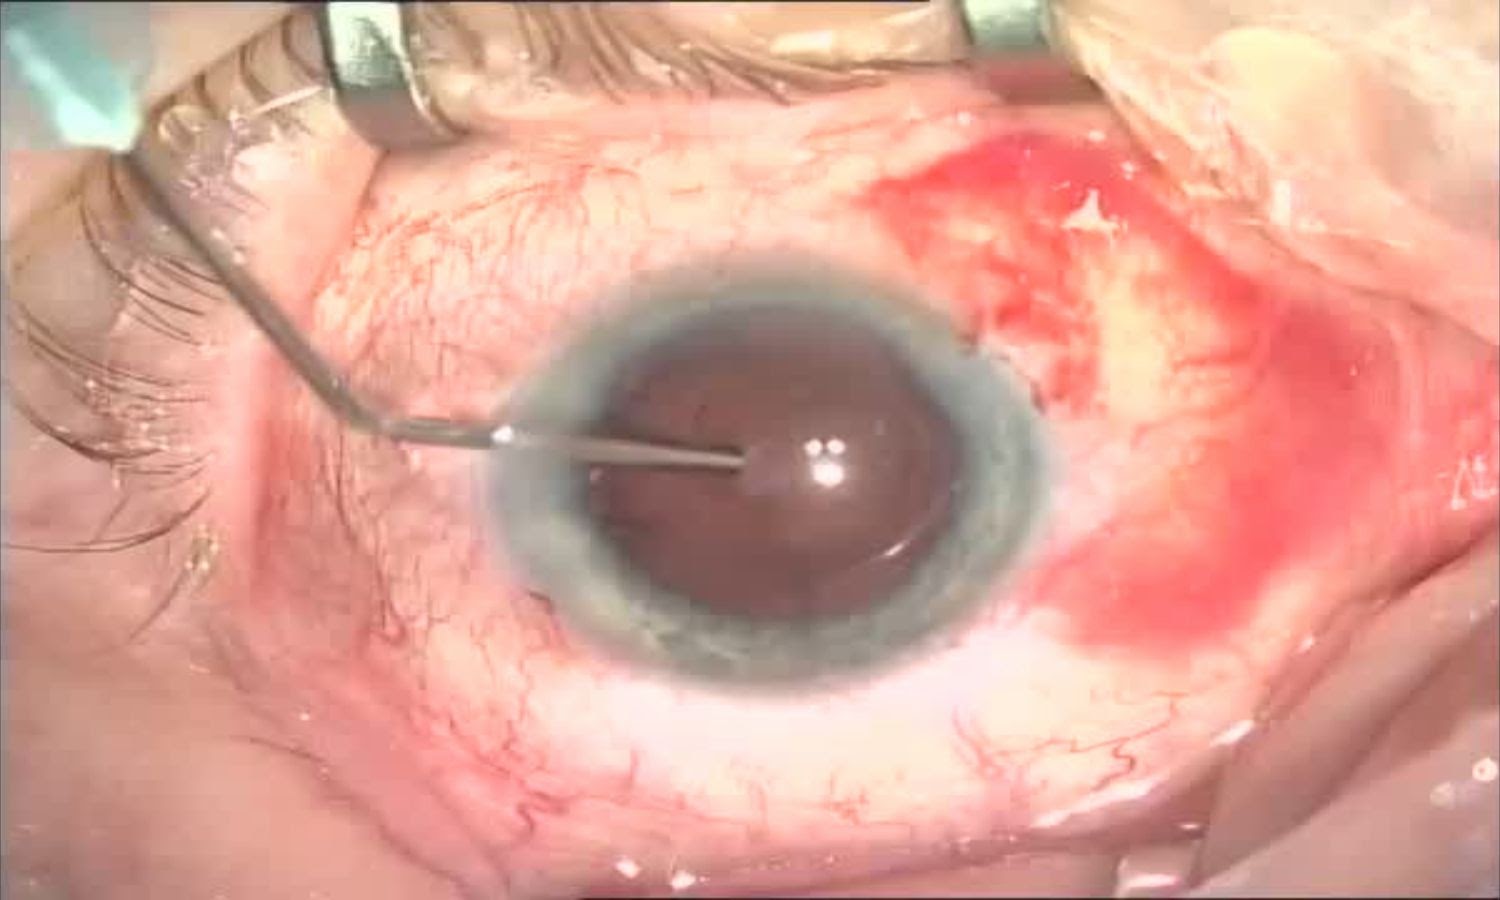

В самом начале операционное поле для стерильности несколько раз обрабатывается кожным антисептиком. Пациент полностью накрывается стерильным покрывалом, чтобы исключить попадание микробов и вирусов в операционное поле. Для глаза в покрывале есть окошко с плёночкой и карманом для сбора жидкости. В ней делается небольшой разрез и его края приклеиваются к ресницам, так как самый большой источник всяких инфекций — это как раз ресницы. Веки раздвигаются при помощи векорасширителя — специаной пружинки, которая известна всем, кто хоть раз ложился на операционный стол у офтальмолога. Всё — случайно моргнуть или закрыть глаз не получится.

Перед Татьяной Юрьевной находится микроскоп — картинка с него через оптический делитель выводится сразу в два места: напрямую хирургу и на матрицу камеры (через которую пишется протокол операции и опционально выводится на внешний экран — как раз с него делались часть фото). Кстати, микроскоп также способен проецировать оси для имплантации, но в глазах после кератотомии Татьяна Юрьевна обязательно дублирует разметку — для осуществления двойного контроля.

Далее этап удаления хрусталика. Чтобы добраться до его внутренностей (ядра и коры) хирург моделирует круглое отверстие в хрусталике в виде круга вручную или специальным лазером. Эта процедура называется круговым капсулорексисом.

Представьте, рукой хирург делает ровный круг диаметром 6—7 мм, вскрывая капсулу толщиной 30 микрон (тоньше человеческого волоса).

Круговой капсулорексис готов:

Форма, размеры и завершение капсулорексиса — очень важная часть операции. Если хирург неумелый, то порвать капсулу можно в два счёта и это сделает операцию осложнённой, а в некоторых случаях её даже невозможно закончить факоэмульсификацией.

Обратите внимание на две фотографии: они отличаются тем, что на первой зрачок красный, а на второй — чёрный. В первом случае на хрусталике ещё присутствует красный свет — по сути, это рефлекс с глазного дна с кровеносными сосудами. Во втором случае хрусталика уже нет и наклон коаксиального осветителя другой — без линзы рефракция меняется и дна мы уже не видим — только саму «дырку» в глазу. Тьма, бездна )